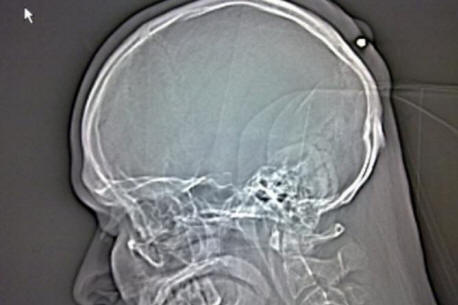

Riferendosi all’ospedale, Autullo si rifiutò di crederlo i dottori lo mostrarono: sulla radiografia era chiaro che un chiodo di ferro di otto centimetri infilato proprio all’interno del cranico scatole di Dante. Prima che l’ambulanza portasse Autullo in un’altra clinica operazione, Dante ha pubblicato una foto di quello sulla sua pagina Facebook immagine a raggi x.